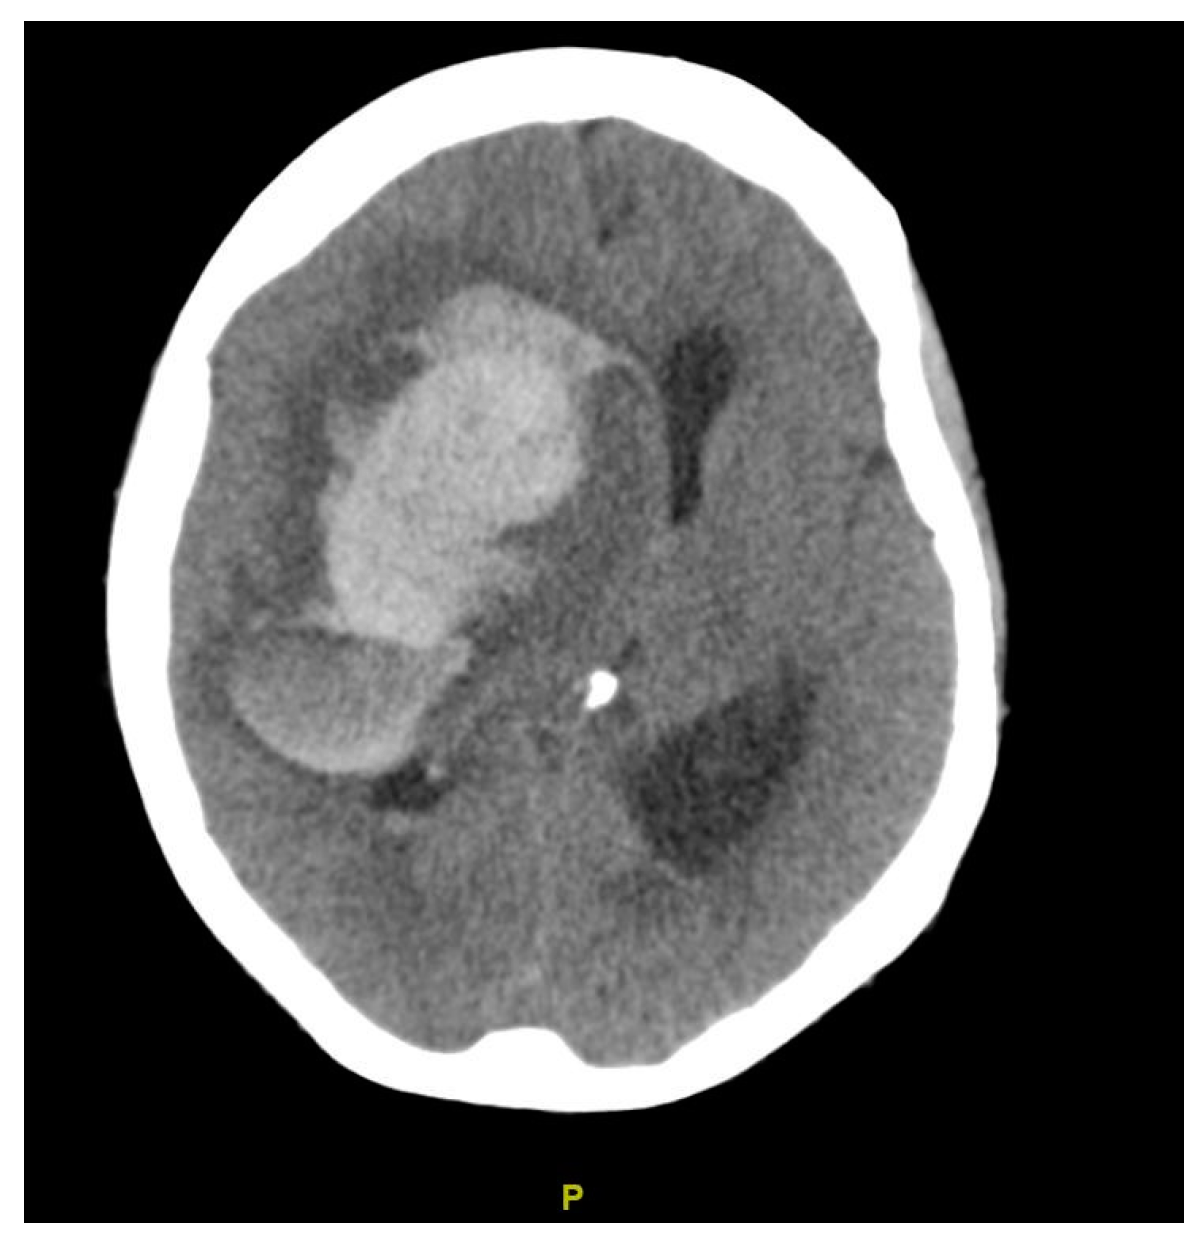

| Diagnosis | Lobar intracranial hemorrhage (ICH) | Basal Ganglia ICH | Lobar ICH | Embolic ischemic stroke (IS) | Embolic IS | |

| Findings | CT: Left occipital intraparenchymal hematoma Volume: 15 mL | CT: Large right frontal temporal parenchymal hematoma, severe surrounding mass effect with leftward midline shift, right uncal herniation Volume: 93.5 mL | CT: Right frontoparietal parenchymal hematoma with locoregional mass effect, rightward midline shift Volume: 25 mL | CT: Left occipital infarct Transcranial doppler: 2 spontaneous emboli, more than 100 high intensity transient signals (HITS) in bilateral middle cerebral arteries (MCAs) after agitated saline | CT: Right parietal lobe hypodensity Transcranial doppler: more than 300 HITS in bilateral MCAs after agitated saline | |